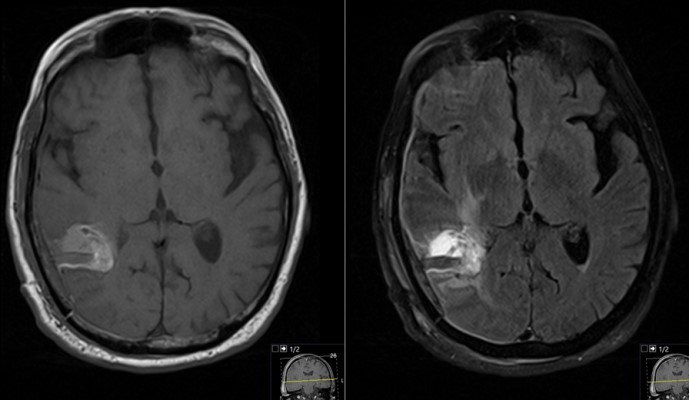

SRS planning images (merged CT & MRI) in the axial (left), coronal (middle) and, sagittal (right) planes with overlapping radiation dosing information. Note the conformity of the Stereotactic Radio Surgery (SRS) dose (demonstrated by the concentric rings around the tumor resection cavity) that treat the tumor bed without exposing the remainder of the brain to high doses of radiation.